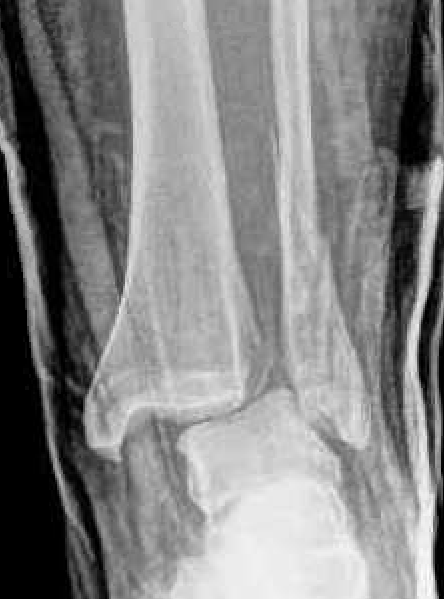

Isolated Weber C fracture

Weber C fracture Weber C fracture with deltoid ligament injury

Maisonneuve injury: proximal fibula with open medial clear space

Xray assessment

| Increased tibio-fibular Clear space | Overlap | Increased medial clear space |

|---|---|---|

|

Medial border of the fibula Lateral border of the posterior tibia (incisura fibularis) Measured 1 cm above the plafond |

Overlap of the fibula and the anterior tibial tubercle | Deltoid ligament injury |

| <5mm AP and mortise |

> 6 mm AP view > 1 mm mortise view |

Maisonneuve / proximal fibular injury |